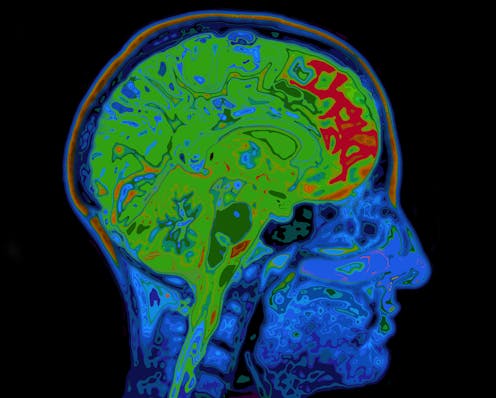

To study glutamate and Gaba, we used a high-strength magnet (called 7-Tesla) to perform magnetic resonance spectroscopy. This technique detects radio frequency electromagnetic signals produced by the atomic nuclei in molecules. This helps scientists to measure what kind of chemicals exist there – and their concentration.

This allowed us to detect and measure glutamate and Gaba levels separately in different brain regions. We specifically looked at two brain regions toward the front of the brain called the anterior cingulate cortex (ACC) and the supplementary motor area (SMA).

That’s because previous studies had already shown that these areas, involved in actions, are affected in OCD. Activity in the ACC changes in response to reward or punishment, guiding future decision-making. The SMA is involved in the coordination of motor sequences and seems to have a role in the production of habits.

We found an imbalance between glutamate and Gaba levels in a group of 31 patients with OCD in the frontal regions of the brain. Specifically, OCD patients had increased levels of glutamate and lower levels of Gaba in the ACC. This means that they had very high levels of neural communication in the area, potentially making it hyperactive. They also had a disrupted balance between these chemicals in the SMA.